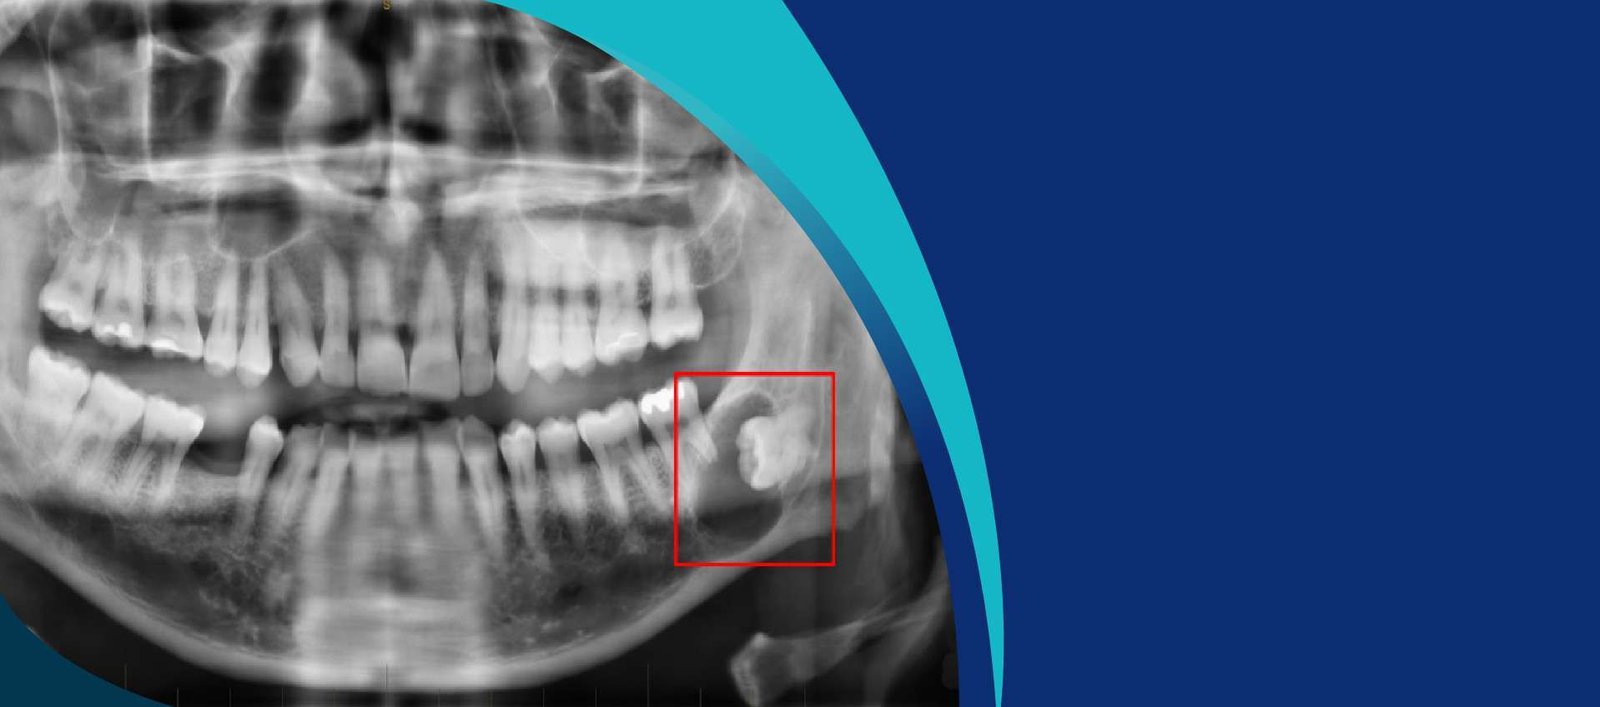

OPG, or Orthopantomogram, is a panoramic scanning dental X-ray of the upper and lower jaw. It provides a wide view of the jaw and teeth, capturing detailed images of the mouth, including the teeth, jawbones, and surrounding structures, in a single, comprehensive image. This technology is instrumental in diagnosing various dental conditions and planning treatments effectively.

• Comprehensive Diagnosis: OPG provides a complete view of your oral structures, enabling our dentists to detect issues such as impacted teeth, jaw fractures, and bone abnormalities.